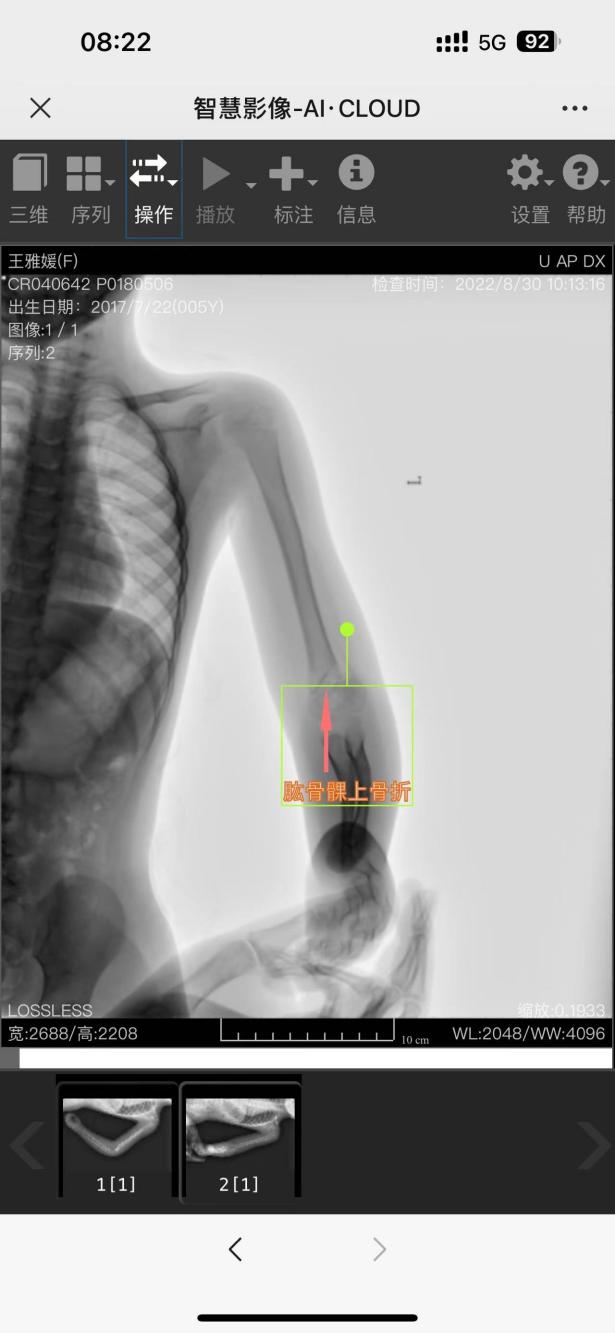

肱骨髁上骨折保守治疗1例

肱骨髁上骨折系指肱骨远端内外髁上方的骨折。以小儿最多见,约占小儿四肢骨折的3%~7%,肘部骨折的30%~40%,其中伸直型占90%左右。

患者性别:王某 ,女

患者年龄:5岁

简要病史:跌倒致左肘部畸形、肿痛、活动受限,就诊于我院,拍片诊断为肱骨髁上骨折,建议手术治疗,患者家属要求保守治疗

予手法复位+夹板外固定+指导患者进行功能锻炼。 最终结果良好。